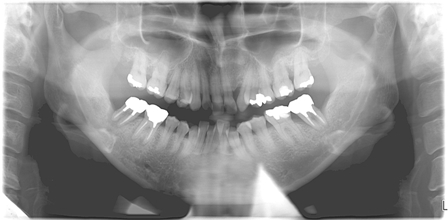

レントゲンでは歯を支えている歯槽骨が吸収を起こしています。特に上下の大臼歯と左上の犬歯が進行しています。